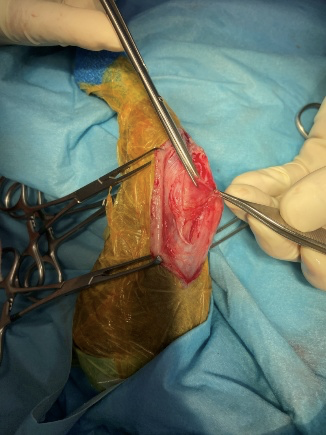

関節包縫合術

膝蓋骨が脱臼することにより緩んだ関節包の一部をメッツェンバーム剪刀で切除し、脱臼する前の状態に近づけます。これにより膝蓋骨が内側に緩みにくくなります。

内側支帯開放術

内側支帯筋の一部である縫工筋前部と内側広筋を関節包から分離し大腿直筋に縫合しています。これにより膝蓋骨を内側に引っ張る力が緩和されます。